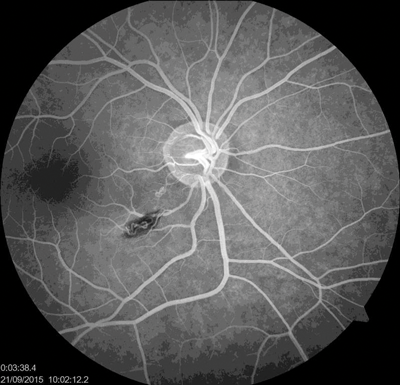

Dilated fundus examination revealed normal findings in the left eye; in the right eye there was partial hemophthalmus, preretinal haemorrhage along the inferotemporal arcade and two vascular anomalies in the inferotemporal arcade and in the papillomacular bundle. Fundus fluorescein angiography (FFA) of the right eye showed rapid filling of vascular anomalies without leakage and with normal arteriovenous transit time (Figure 1). No intervening capillary plexus was noted. FFA of the left eye was normal.

Figure 1: Rapid filling of vascular anomalies without leakage.